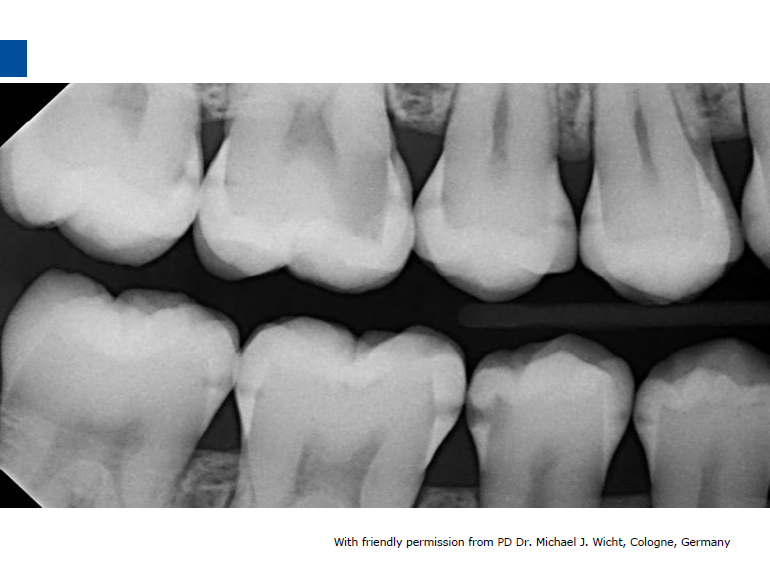

微创牙科治疗是一种全新的龋病治疗理念,着眼于疾病的早发现、早诊断、早治疗。树脂渗透治疗是介于再矿化治疗和充填治疗之间的一种创新的治疗手段,通过微量的去除牙体组织,达到加固脱矿釉质、阻止进一步脱矿的目的。

lcon渗透基于封闭釉质龋空隙的一种特殊树脂的渗透,封闭釉质龋小孔,从而阻断致龋酸传播途径,阻止龋病进一步发展。这种材料操作方法简单,对牙体组织损伤轻微,不用通过麻醉和磨切牙体来达到加固脱矿釉质,同时可以改变釉质龋表面的白色或棕色改变,达到美观修复效果,是对龋病微创治疗的突破。

一、爱康渗透树脂邻面装Icon Caries Infiltrant – approximal治疗早期邻面龋

治疗套装中的注射器含有足够治疗两处病变部位的材料,使用后即丢弃。亦可在一次治疗中连续处理多个邻面龋。